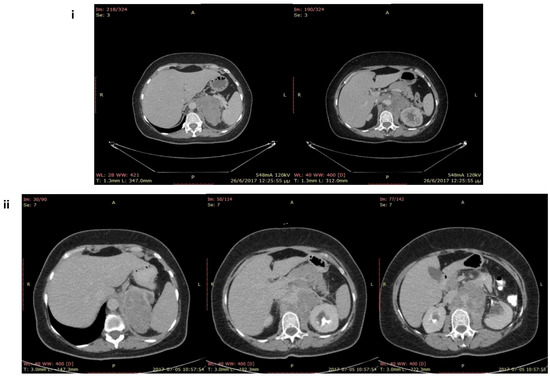

Case Report

Primary Adrenal Lymphomas with Cushing’s Syndrome: Two Cases with Evidence of Endogeneous Cortisol Production by the Neoplastic Lymphoid Cells

by Sotirios G. Papageorgiou, Ioanna Mavroeidi, Marios Kostakis, Aris Spathis, Danai Leventakou, Evangelia Kritikou, Nikolaos Oikonomopoulos, Chrysoula Kourkouti, Maria Krania, Anthi Bouchla, Thomas Thomopoulos, Zoi Tsakiraki, Konstantinos Markakis, Ioannis G. Panayiotides, Nikolaos Thomaidis, Vasiliki Pappa, Periklis G. Foukas and Melpomeni Peppa

J. Clin. Med. 2023, 12(15), 5032; https://doi.org/10.3390/jcm12155032 - 31 Jul 2023

Primary adrenal lymphoma (PAL) is a rare entity that presents as unilateral or bilateral rapidly growing adrenal masses, with signs and symptoms most commonly related to adrenal insufficiency due to the mass effect on the surrounding tissues. Although steroeidogenesis has not been previously [...] Read more.

Primary adrenal lymphoma (PAL) is a rare entity that presents as unilateral or bilateral rapidly growing adrenal masses, with signs and symptoms most commonly related to adrenal insufficiency due to the mass effect on the surrounding tissues. Although steroeidogenesis has not been previously described in PAL, we herein report two cases of PAL presenting as adrenal incidentalomas (AIs) that demonstrated autonomous cortisol production. A 52-year-old woman presented with lumbar pain; a computed tomography (CT) scan demonstrated a left AI measuring 8.5 × 15 × 10 cm. Similarly, an 80-year-old woman presented with lumbar pain, demonstrating in a CT scan a bilateral AI (right: 9 × 6.5 cm, left: 3.6 × 3.2 cm). Both cases underwent a full hormonal evaluation according to the algorithm for the investigation of AIs, demonstrating increased 24-h cortisol excretion, suppressed fasting adrenocorticotropic hormone (ACTH) levels, and non-suppressed serum cortisol levels in both the overnight and the low-dose dexamethasone suppression tests, indicating autonomous cortisol secretion and Cushing’s syndrome. In a relatively short time, both patients developed night sweats, and their clinical picture deteriorated, while the CT scans showed increased dimensions of the masses with radiological characteristics compatible to lymphoma. Both patients underwent ultrasound-guided biopsies (FNBs), revealing infiltration of the left adrenal by diffuse large B-cell lymphoma in the first case, whereas bilateral adrenal infiltration from the same histological type was noted in the second case. Subsequently, they were treated with immunochemotherapy, but the second patient died from an infection shortly after the initiation of the treatment. To our knowledge, this is the first report of PAL presenting with Cushing’s syndrome due to autonomous cortisol production, indicating that neoplastic lymphoid cells in PAL might acquire the potential for steroidogenesis; therefore, more cases of PAL should be analyzed so as to further elucidate the complex pathogenesis and the natural course of this entity. Full article

(This article belongs to the Section Hematology)

Show Figures

Figure 1